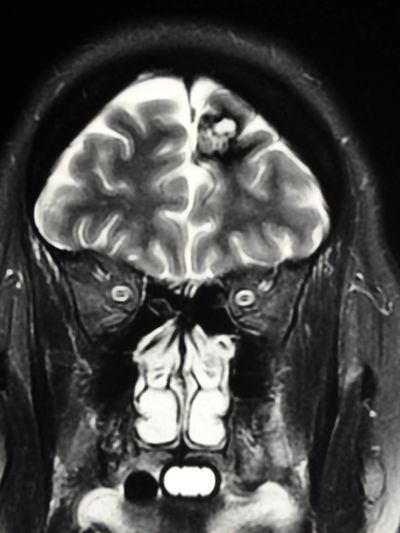

Chiari malformation is a condition where the cerebellar tonsils, located at the back of the brain, herniate downward into the spinal canal. This can lead to the compression of brain tissue and disturbances in the flow of cerebrospinal fluid. The severity and specific symptoms of Chiari malformation can vary depending on the type and extent of the herniation. Common symptoms of Chiari malformation include:

Diagnosing Chiari malformation involves a combination of medical history evaluation, neurological examination, and imaging studies. The diagnostic process aims to assess the structure of the brain, the presence of herniation, and any associated abnormalities. The steps for diagnosing Chiari malformation typically include:

Imaging Studies: